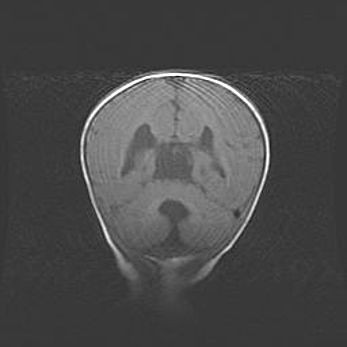

Мальформация Денди-Уокера. Киста задней черепной ямки.

Агенезия мозолистого тела.

Возраст: 2,5 месяца

Вес: 2420 г

Пол: женский

Окружность головы: 37 см

Срок гестации: 32 недели

Мальформация Денди—Уокера — редкий вид патологии ЦНС, представляющий собой врожденный порок развития каудального отдела ствола и червя мозжечка, ведущий к неполному раскрытию срединной (Мажанди) и латеральных (Лушка) апертур IV желудочка мозга. Для этогно синдрома характерна триада симптомов: гипотрофия червя мозжечка и/или полушарий мозжечка, кисты задней черепной ямки, гидроцефалия различной степени. В 70% случаев порок сочетается и с другими аномалиями головного мозга, в частности с агенезией мозолистого тела.